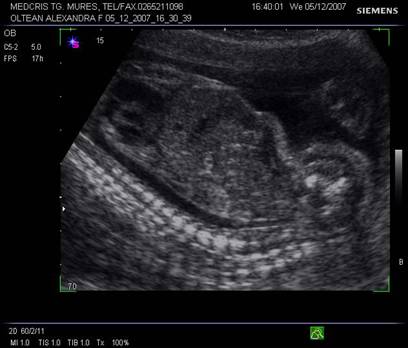

Planul VIII defineste profilul fetal in pozitie occipitoposterioara. Profilul de-vine vizibil de la sfarsitul trim I. In aceasta sectiune se pot oserva miscarile fiziologice fetale de deschidere a gurii, miscarea limbii, inghitirea, aspiratia de lichid amniotic.

Pozitia favorabila fetala poate pune in evidenta cavum septum pellucidi, corpus calosum (dupa 20 de sapt), lamina tecti, pons sau cerebellum.

Fig. nr.158 Profil fetal in pozitie occipitoposterioara, corespunzator planului VIII